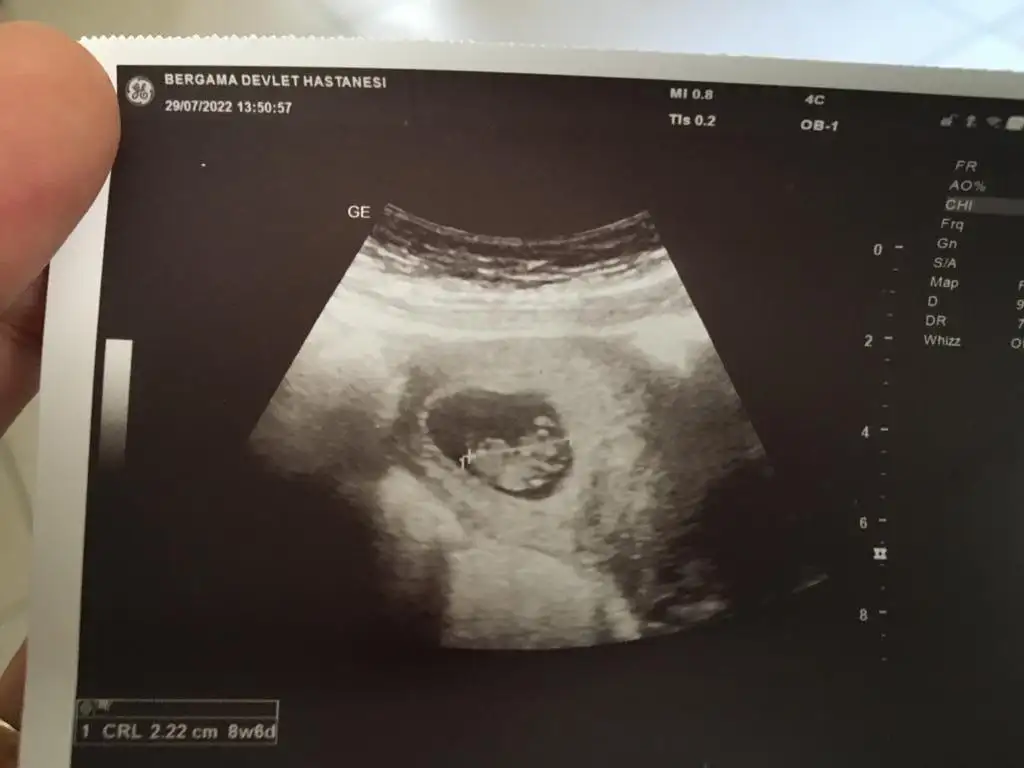

Merhaba 9+3 karından

• IMG-20220729-WA0005.webp

17,5 KB · Görüntüleme: 99